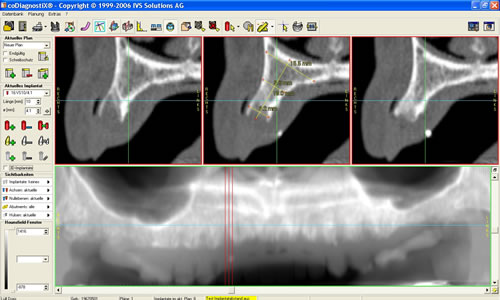

Mit der Entwicklung der Computertomographie (CT) und in jüngerer Vergangenheit der digitalen Volumentomographie (DVT) stehen Untersuchungsverfahren zur Verfügung, mit denen sehr viel einfacher und genauer das Knochenangebot vermessen werden kann. Von dem Patienten wird in einer Klinik oder Praxis, die über die entsprechenden Möglichkeiten verfügt, ein Spezialröntgenbild (DVT/CT) des Ober-, seltener des Unterkiefers, angefertigt. Dieses spezielle Röntgenbild dauert für einen Kiefer 20 Sekunden. Der große Vorteil liegt darin, dass der gesamte Kiefer durch den Computer in über 100 Schnitten abgebildet werden kann. Auf diesen Schnittbildern können Höhe und Breite des Knochens direkt abgemessen werden (Abb. 5.5).

Nach dem Überspielen der Daten auf den Praxiscomputer des Zahnarztes eröffnen sich weitere Möglichkeiten. Der Kiefer wird in verschiedenen Ebenen gleichzeitig dargestellt und damit eine räumliche Auswertung möglich. Neben der Vermessung des Kiefers kann die Knochenqualität durch Dichtemessungen beurteilt werden. Damit lässt sich z.B. eine bestimmte Knochenerkrankung, die Osteoporose, nachweisen bzw. ausschließen.

Am Praxiscomputer lassen sich Besonderheiten des jeweiligen Patienten herausarbeiten, wie z. B. die Beschaffenheit der Nasennebenhöhle. Hier können verschiedenen Knochenleisten (Abb. 5.6) oder Schleimhautveränderungen das Implantieren erschweren. Umso wichtiger ist es durch ein Computertomogramm diese Variationen vor der Implantation zu kennen. In den speziellen Programmen können bereits Implantationen simuliert werden (Abb. 5.7, 5.8).

Abb. 5.7: Implantations- simulation am PC.

Abb. 5.8: Implantatplanung.

Dabei werden das Implantat, die richtige Länge und der geeignete Durchmesser ausgewählt. Entscheidend ist auch die Richtung, in der implantiert werden muss. Auch dies lässt sich bereits am Computer auf den Schnittbildern simulieren. Eine dreidimensionale Darstellung des Knochens und die Möglichkeit das äußere Profil zu zeigen, verdeutlichen den späteren Sitz der Implantate und die Beziehung zum Gegenkiefer, zur Kauebene, zu Wangen und Lippen lassen die spätere Versorgung kosmetisch vorhersehen (Abb. 5.9, 5.10). Eine Dichtemessung um die Implantate schließt die Planung ab.

Mit diesem Untersuchungsverfahren ist die Implantation auch bei schwierigen Situationen möglich und sehr sicher geworden.

Im Oberkiefer wird diese Untersuchung und Planung in unserer eigenen Praxis seit Jahren routinemäßig durchgeführt. Die erheblich verbesserten Ergebnisse rechtfertigen den Mehraufwand, die geringfügig höhere Strahlenbelastung der heutzutage modernen Geräte sowie die Kosten, die dadurch entstehen.